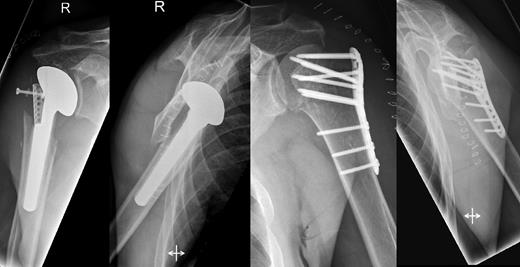

A 48-year-old patient was referred to a level I trauma center after the first incidence of an epileptic convulsion. The patient was alert and oriented with retrograde amnesia from the time of convulsion. Peripheral neurology was normal. The X-rays showed bilateral posterior shoulder dislocation with fractures of both humeral heads (Fig. 1). A CT of the head and both shoulders was performed to exclude intracerebral pathology and to achieve better demonstration of the shoulder fractures (Fig. 2). According to the AO fracture classification, he had a 11-C3.1 fracture on the left side and a 11-C3.3 fracture on the right side. The right side fracture was treated with a cementless hemiarthroplasty (OrTra®, Zimmer, Germany), while an open reduction and internal fixation (ORIF) with an angular stable plate (Philos®, Synthes, Germany) was performed on the left. Despite the high incidence for humeral head necrosis after ORIF in this fracture type, this option was chosen based on the young age of the patient. Postoperative X-rays and CT showed adequate positions of the implants (Fig. 3). The shoulders were immobilized in Gilchrist bandages followed by passive mobilization for the first 6 weeks by physiotherapy with a limitation for abduction and anteversion to 90°. There were no complications intraoperatively or in the first postoperative time. Patient was discharged after 8 days. Antiepileptic therapy was initiated with 5 mg clobazam and subsequent increasing doses over the following weeks. There were no more signs of epilepsy in the follow-up. A CT 4 months after operation showed dislocation of a fragment on the left side which was subsequently resected. At the 1-year postoperative review, the patient showed impingement of the left shoulder with abduction limited to 50° by both the plate and an osteophyte. Radiological assessment revealed signs of necrosis of the head. The plate was removed and the osteophyte resected. Eighteen months after injury, the left shoulder showed progressive avascular osetonecrosis of the head (Fig. 4) and after plate removal an inversed prosthetic replacement had to be performed (Fig. 5). At the last follow-up 3 years after injury, the patient was free of pain with a bilateral range of motion of 90° abduction and elevation.

Avascular head necrosis over the following one and a half years on the left side with ongoing necrosis after plate removal.